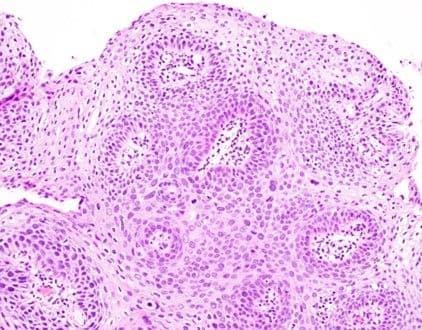

Adenocarcinoma in situ (AIS) is the precursor of invasive endocervical adenocarcinoma. Microscopically, AIS has preserved endocervical gland architecture (Figure 10) but with varying degrees of atypia (e.g., nuclear enlargement and stratification, nuclear hyperchromasia, apical mitotic figures, and basal apoptoses) (Figure 11A, 11B).

Figure 10

Partial gland involvement by AIS is common and can be highlighted by positive p16 immunostaining in the lesional cells (Figure 12A, 12B). AIS is most commonly identified at the transformation zone and may spread up to 3 cm upward in the endocervical canal [83]. Importantly, AIS may be multifocal, and it is not unusual to find residual tumor after negative conization margins [84].

Figure 12